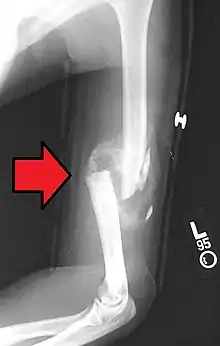

A displaced supracondylar fracture in a child